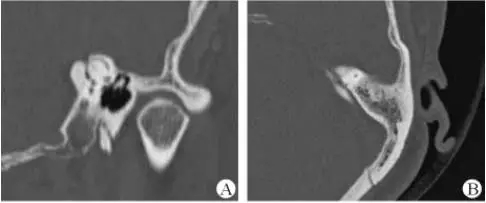

1、上半規(guī)管裂綜合征

內(nèi)耳結(jié)構(gòu)非常微妙。即使是內(nèi)耳中大頭針樣的孔洞也能造成平衡失調(diào)。患者常常不敢進行如走路或轉(zhuǎn)頭的日常活動。此罕見疾病,醫(yī)學專家預估至少影響著人口的1%。可造成惡心,眩暈以及對噪聲極高的敏感性。病人還常常抱怨他們能聽到血管跳動的聲音。其中一位患者曾告訴耳科專家,他都能聽到自己轉(zhuǎn)動眼睛的聲音。

診斷及治療

醫(yī)生若懷疑此病將會安排內(nèi)耳CT掃描。在大多數(shù)案例中,一旦此病被耳鼻喉科醫(yī)生或其它聽力健康專家確診,則可實行手術治療。外科手術風險包含聽力損失以及神經(jīng)損傷;重建及復原需內(nèi)耳的治療以及大腦的重塑。

2、膽脂瘤

另一個不常見的疾病叫膽脂瘤,發(fā)病率為1/10000,這個“腫瘤”在內(nèi)耳中逐漸生長。盡管不是惡性的,但也能導致永久性的聽力損失以及其它嚴重的疾病,比如腦膜炎。癥狀是有臭味的耵聹以及聽力損失。